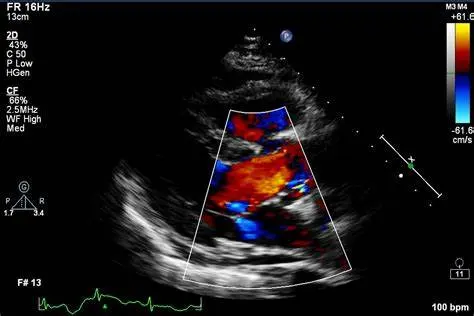

Immagine ecografica del cuore.

Ecocardiogramma color-Doppler

L’ecocardiogramma usa ultrasuoni per creare immagini del cuore, valutando struttura e funzione. Può diagnosticare problemi alle valvole, dimensioni e funzioni cardiache, cardiopatie congenite, trombi, e monitorare il recupero post-operatorio. Non invasivo e sicuro, fornisce immagini in tempo reale per diagnosi accurate e trattamenti efficaci.